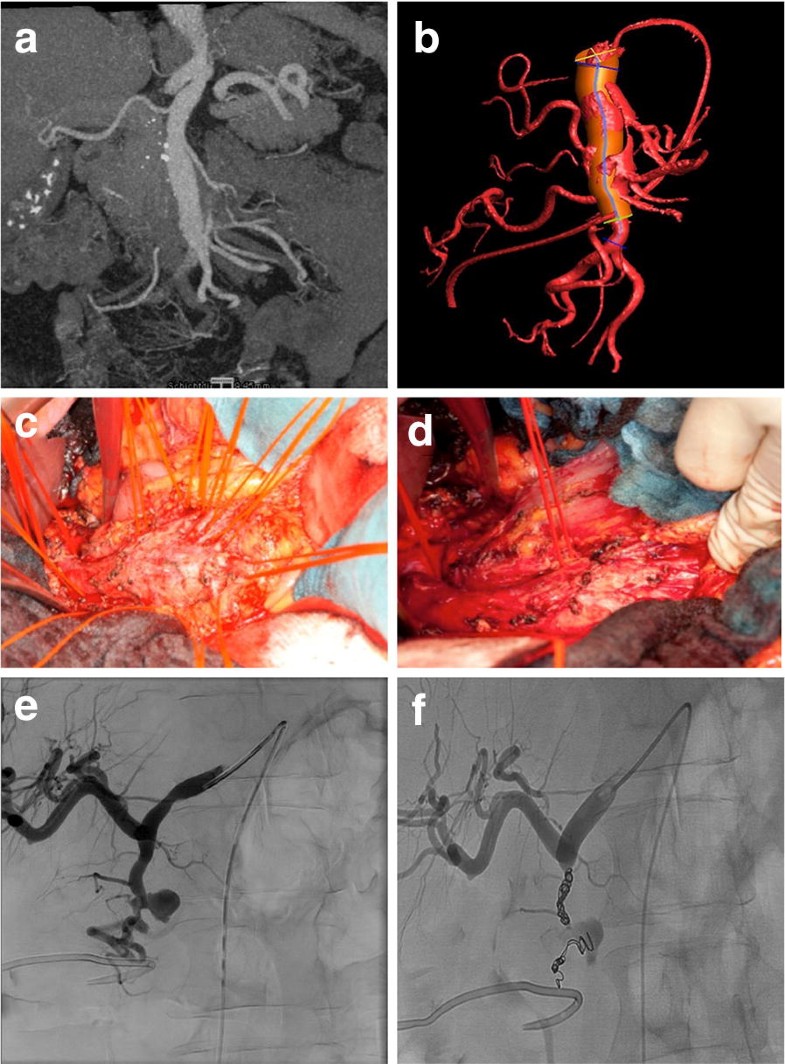

From eurjmedres.biomedcentral.com

Visceral artery aneurysms evolving interdisciplinary management and Coiling Coronary Aneurysm Treatment options include medical management, surgical excision, coronary bypass grafting (cabg), and percutaneous coronary. Aneurysmal dilation of coronary arteries is found in up to 5% of patients undergoing coronary angiography (1). The vast majority of coronary artery aneurysm and coronary artery ectasia is detected incidentally during coronary angiography or computed tomography. Coronary artery aneurysms (caas) are uncommon and describe a. Coiling Coronary Aneurysm.